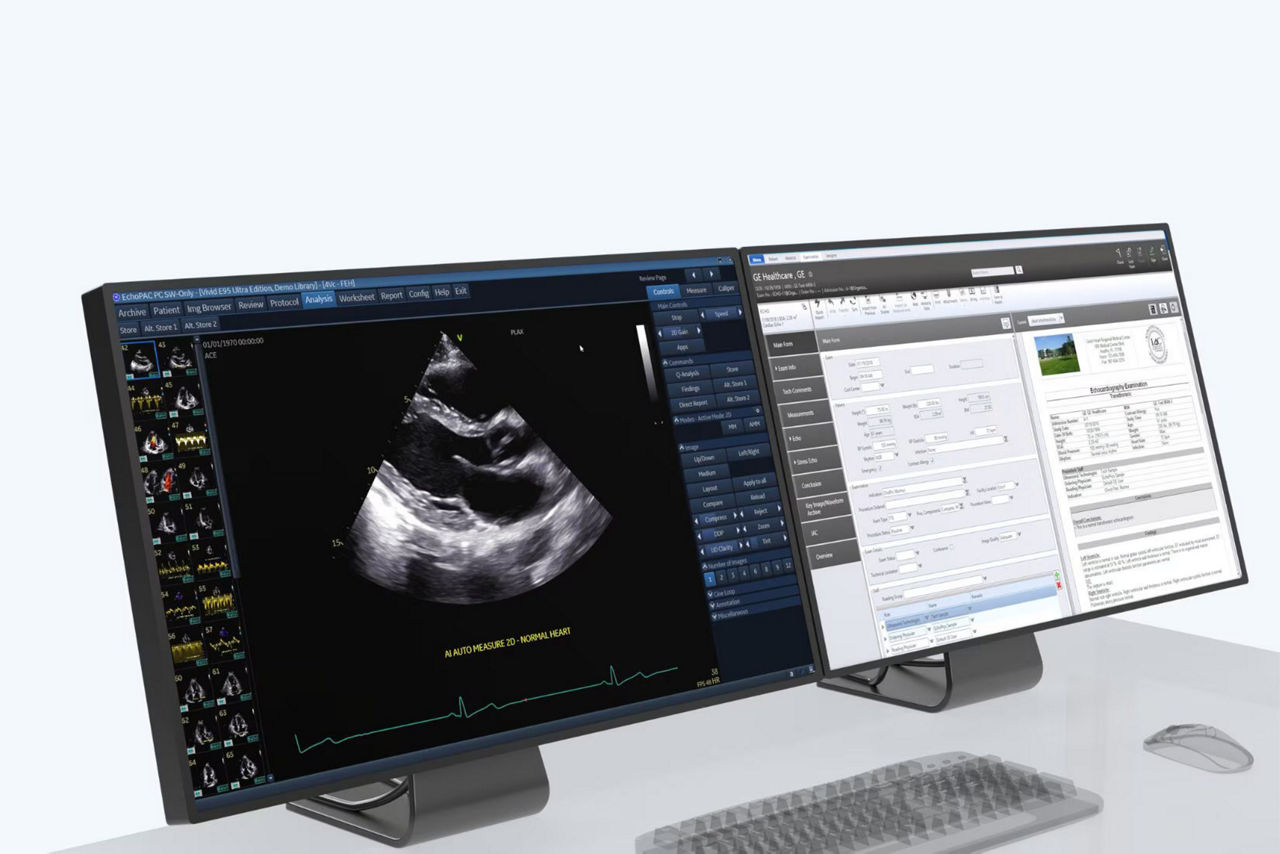

EchoPAC™

Seamless integration with post-processing and review workflows through open 4D multivendor

EchoPAC Software Only and EchoPAC Plug-in allow users to analyze and review data from any Vivid ultrasound system, as well as DICOM images from other ultrasound systems. DICOM SR Measurement Transfer, including standard and custom measurement allows seamless integration with GE Healthcare and other industry reporting systems and EMRs.